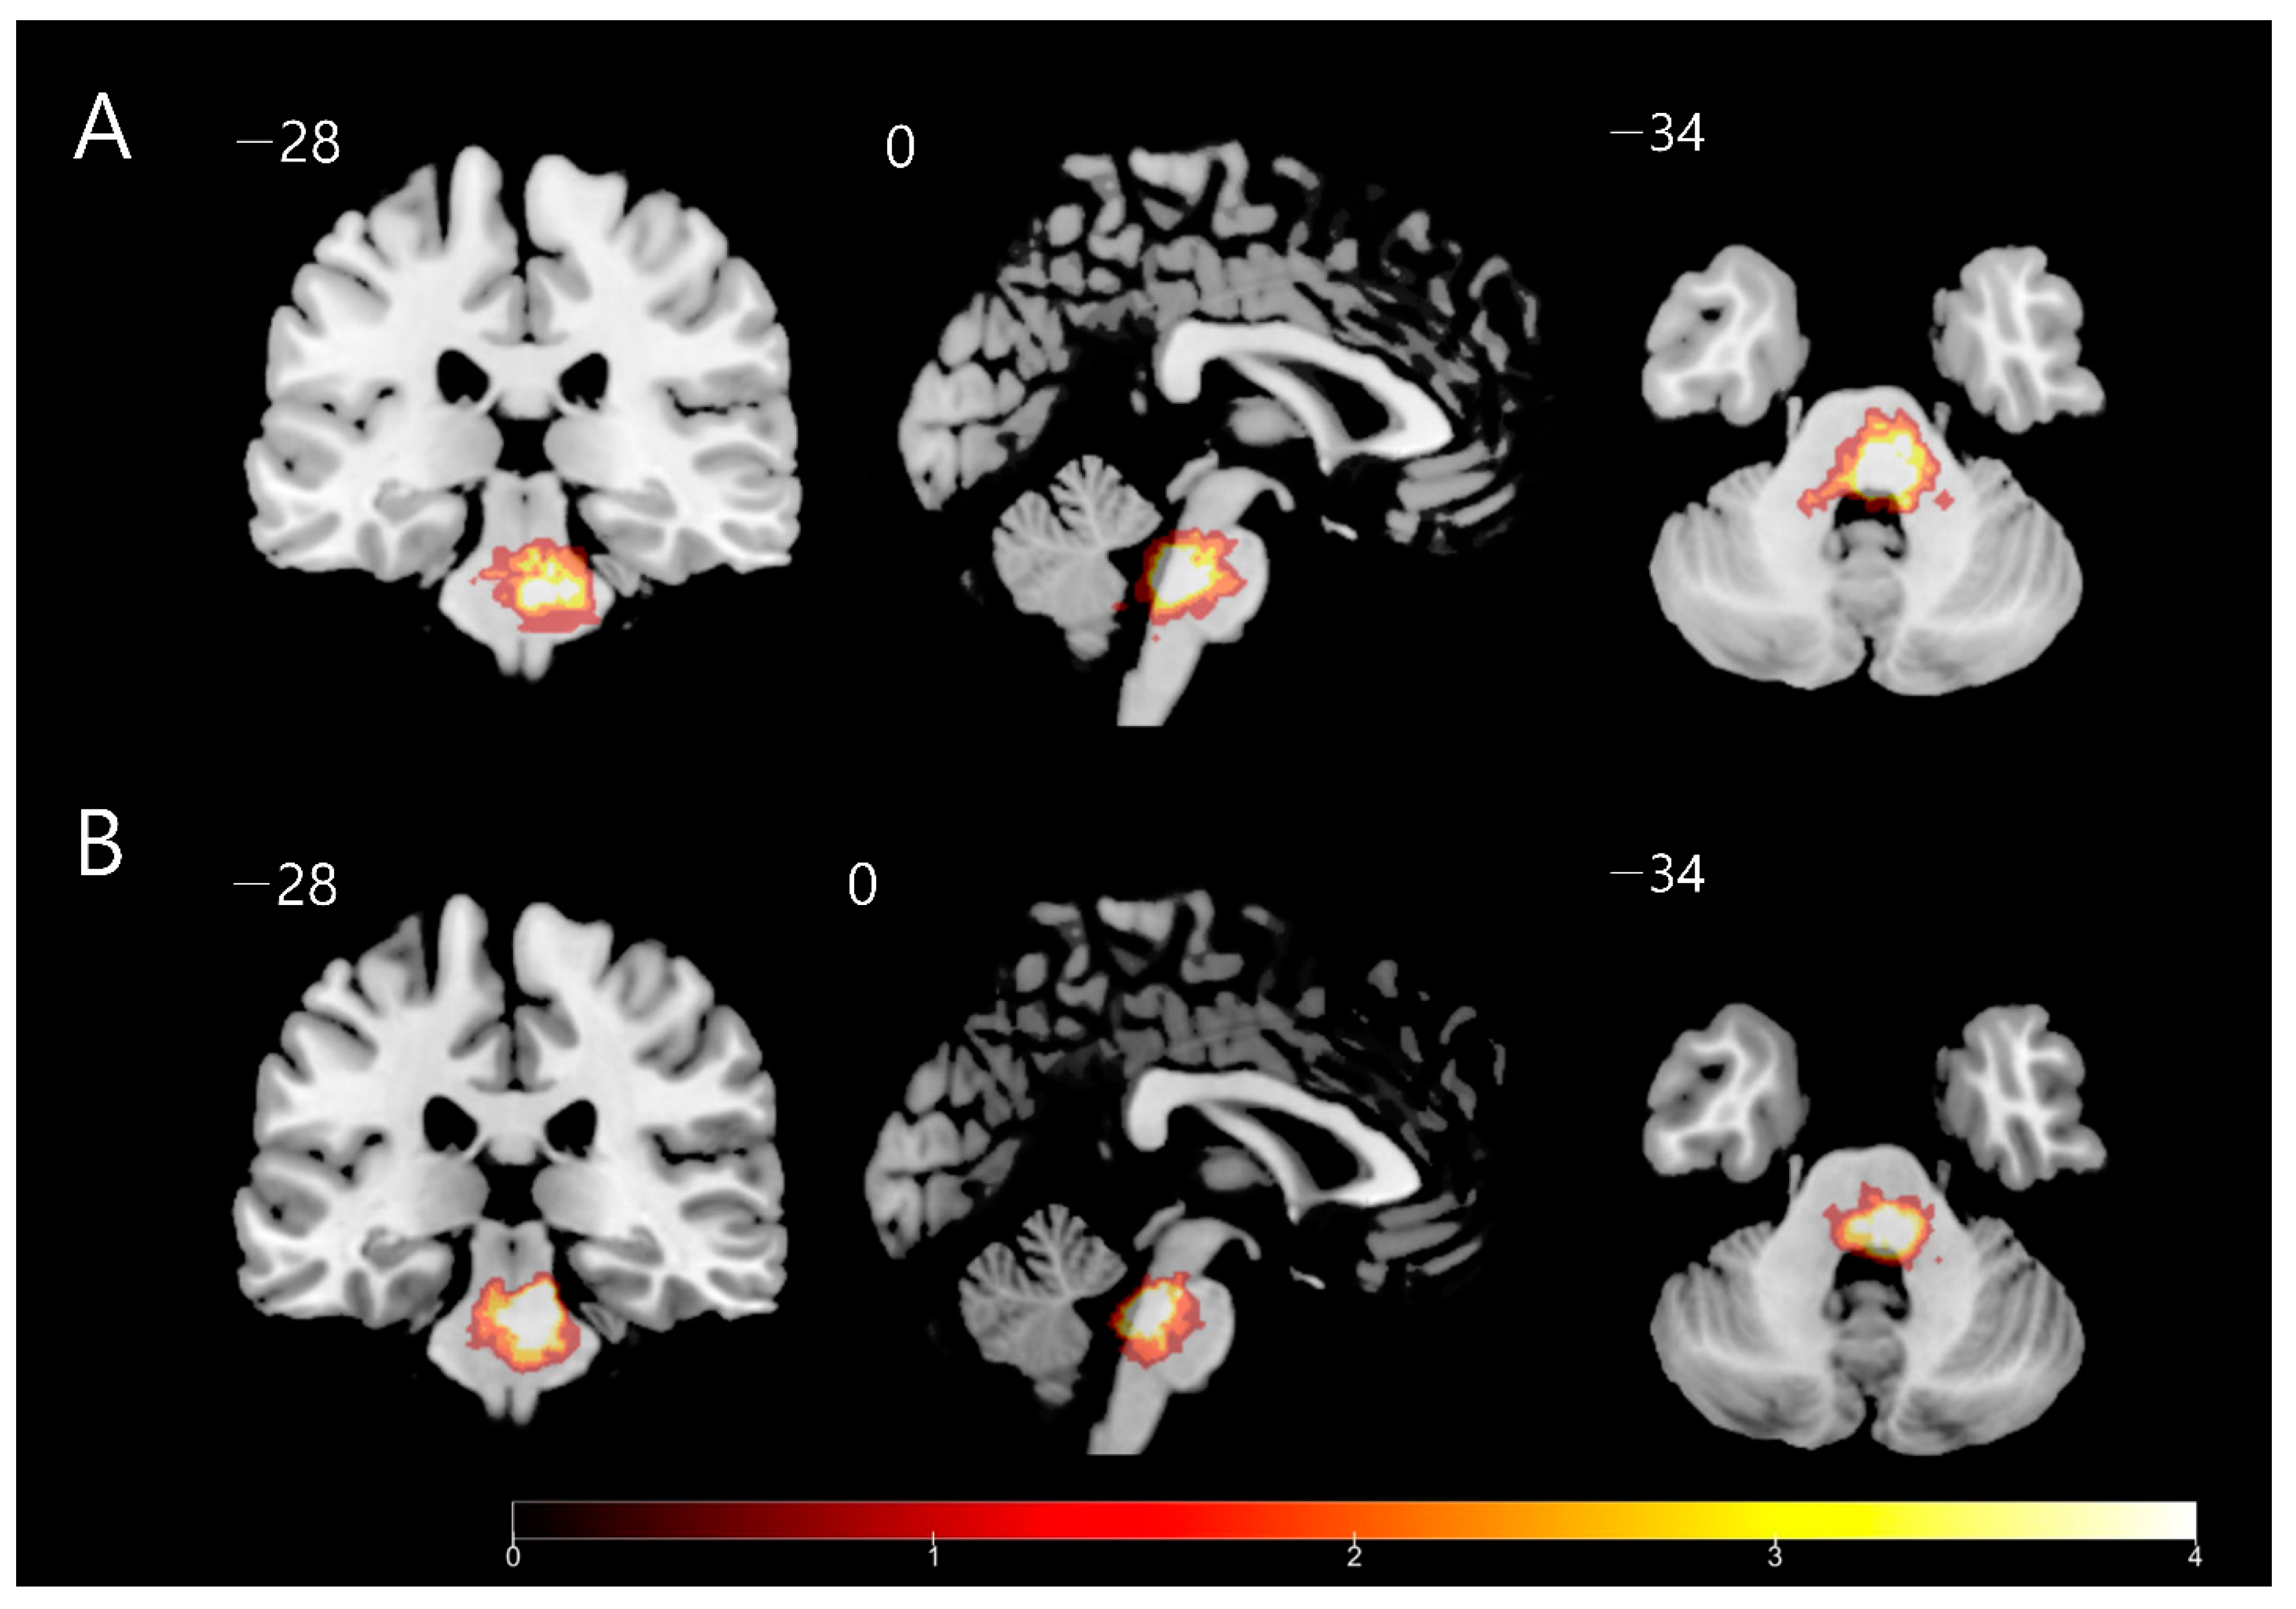

| Metabolism | Area | Coordinate | t Score | z Score | Cluster | ||

|---|---|---|---|---|---|---|---|

| x | y | z | |||||

| Decreased | Contralesional Anterior Cingulum | −14 | 42 | 14 | 4.58 | 3.94 | 269 |

| Ipsilesional primary motor cortex | 38 | 0 | 38 | 3.84 | 3.42 | 224 | |

| Increased | Ipsilesional cerebellum | 30 | −36 | −30 | 4.04 | 3.57 | 179 |

| Contralesional cerebellum | −10 | −8 | −52 | 3.92 | 3.48 | 292 | |